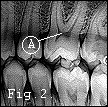

If you eat too many of the 'nice but naughty' foods over Christmas you may need a trip to the man / woman you may dread to visit .... the dentist. The image right shows a dental X-ray of teeth. Read Maurice's Nightmare Article on how he got on with his dentist and learn a bit more about the teeth and their care.